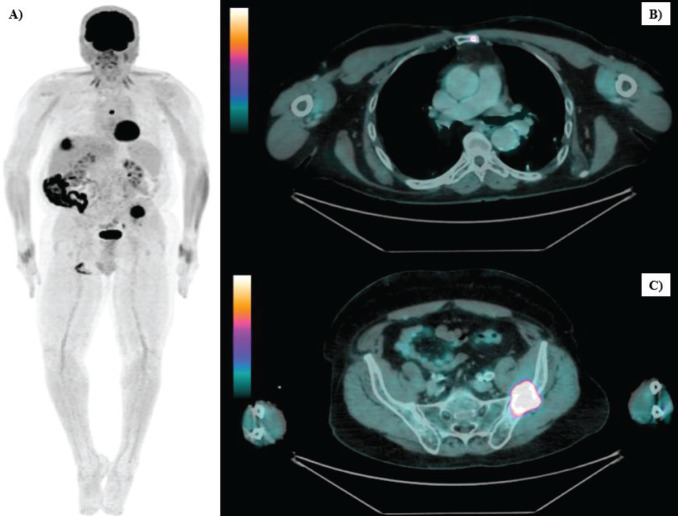

Methods: We reported a case of a 64-year-old male with locally advanced LC who developed oligometastatic disease in the bones and liver 21 months after concurrent cisplatin-based chemoradiotherapy. Initially, due to negative PD-L1 expression, the patient was treated docetaxel, cisplatin and cetuximab combination. Chemotherapy after 10 months, new hepatic progression was confirmed by biopsy. Given the asymptomatic, single-site progression in a cirrhotic liver, microwave ablation was performed. Isolated bone progressions were treated with stereotactic body radiation therapy at 2 and 4 months, and nivolumab replaced cetuximab.

Results: The patient has shown no evidence of disease progression for 22 months, with excellent tolerance.

Conclusion: The synergy between nivolumab and local therapies appears promising for managing oligometastasis in laryngeal cancer.